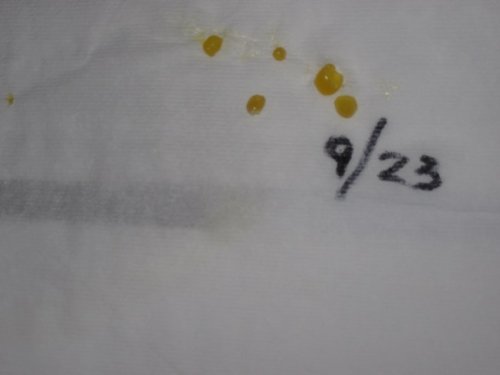

she looks great, has not missed a meal yet, but there was just enough off in her, not acting herself, plus- her belly- I was really hoping for a clear ultrasound, but in my heart , I knew better  I am so sad for her- she went to the vet, had her ultrasound- we could not tell how many, but for sure she has more- so we gave her a cal/ injection, and I took her home, and started the Oxycontin injections - she has passed 5 more slugs so far- so that is 27 slugs so far- this is a HORRIBLE thing to watch , she is making her noise again, but I know this is what is needed for her to live - but it breaks my heart to watch - this is a pic of the ultrasound - you can see some of the eggs - will keep you all posted- its going to be a long night

I am so sad for her- she went to the vet, had her ultrasound- we could not tell how many, but for sure she has more- so we gave her a cal/ injection, and I took her home, and started the Oxycontin injections - she has passed 5 more slugs so far- so that is 27 slugs so far- this is a HORRIBLE thing to watch , she is making her noise again, but I know this is what is needed for her to live - but it breaks my heart to watch - this is a pic of the ultrasound - you can see some of the eggs - will keep you all posted- its going to be a long night  if she can not pass these all, I am going to have her spayed - its the only last choice - but good Lord, just how many more of these *#^&*!! things can she have!

if she can not pass these all, I am going to have her spayed - its the only last choice - but good Lord, just how many more of these *#^&*!! things can she have!